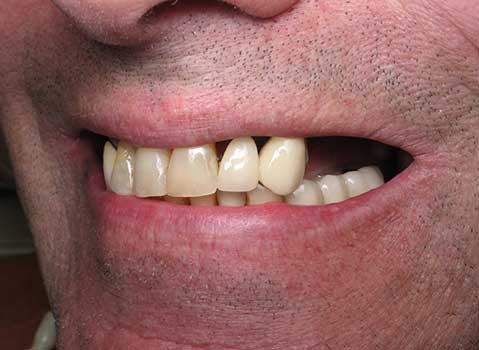

Corey E.

This patient had lost his front tooth due to an accident and had an Implant placed to replace it.